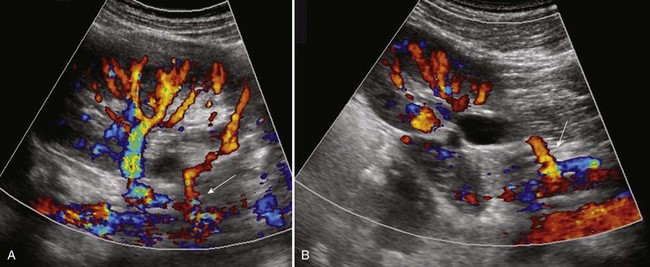

Once URA is diagnosed, a retroperitoneal ultrasonogram with color Doppler will show absence of the kidney and ipsilateral renal vessels. A plain film of the abdomen showing the gas pattern of the splenic flexure in the left renal fossa suggests left renal agenesis, ectopia, or crossed ectopia (Mascatello and Lebowitz, 1976), whereas the gas pattern of the hepatic flexure positioned in the right renal fossa suggests congenital absence of the right kidney (Curtis et al, 1977). The diagnosis of URA usually can be confirmed with a DMSA scan showing absent uptake of the isotope on one side, with the contralateral kidney often showing compensatory hypertrophy (Hynes and Watkin, 1970; Cope and Trickey, 1982). A DMSA scan will also detect an ectopic (usually pelvic) or a crossed ectopic kidney in cases where the nonvisualized orthotopic kidney is thought to be absent (Volkan, 2003). In some cases, crossed fused ectopia may be difficult to distinguish from a congenital solitary kidney that has undergone compensatory hypertrophy or a solitary complete duplication. A small dysplastic kidney or MCDK may be misdiagnosed as URA when a kidney is not seen on ultrasonography (Mesrobian, 1993). In these cases, the colonic gas pattern will not be observed in the renal fossa. In addition, calcifications in the renal fossa may suggest an involuted MCDK (Nakano et al, 1996).

Ultrasonography, radionuclide scintigraphy, and MRI have replaced arteriography in diagnosing URA. When a fetus with other suspected organ anomalies undergoes MRI, an absent kidney can be confirmed (Dell’Acqua et al, 2002). URA has also been found incidentally during fluoroscopic monitoring of the renal fossa at the end of a cardiac catheterization or at the end of an echocardiogram. When URA is diagnosed, a voiding cystourethrogram should be performed, because there is a 28% incidence of contralateral reflux (Cascio et al, 1999; Kaneyama et al, 2004).

Renovascular hypertension secondary to an anomalous blood supply has been reported, but a higher-than-normal incidence is yet to be proved. A recent study by van den Bosch and colleagues (2010) examined the urologic and nephrologic consequences of both simple and crossed renal ectopia. They found no adverse effects on blood pressure or kidney function during childhood. They did note that although global renal function of these kidneys was normal, the relative function of the ectopic kidney on dimercaptosuccinic acid scan (99mTc-DMSA) was 38% (interquartile range [IQR] 33% to 43%).